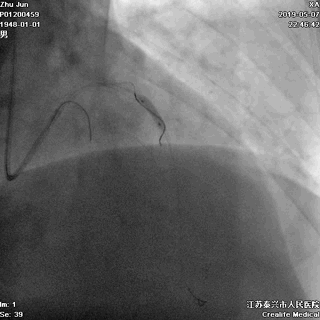

一、指引导管到位

---防止导管嵌顿和深插

主干开口病变,指引导管嵌顿或深插,就可能一招致命

游离一根导丝至升主动脉,防止导管深插

轻轻冒烟,证实指引导管到位

轻轻冒烟,大致了解前降支的情况

这一步相当重要。否则,无论是导管嵌顿,还是导管深插,稍不留意患者都有可能一招致命。